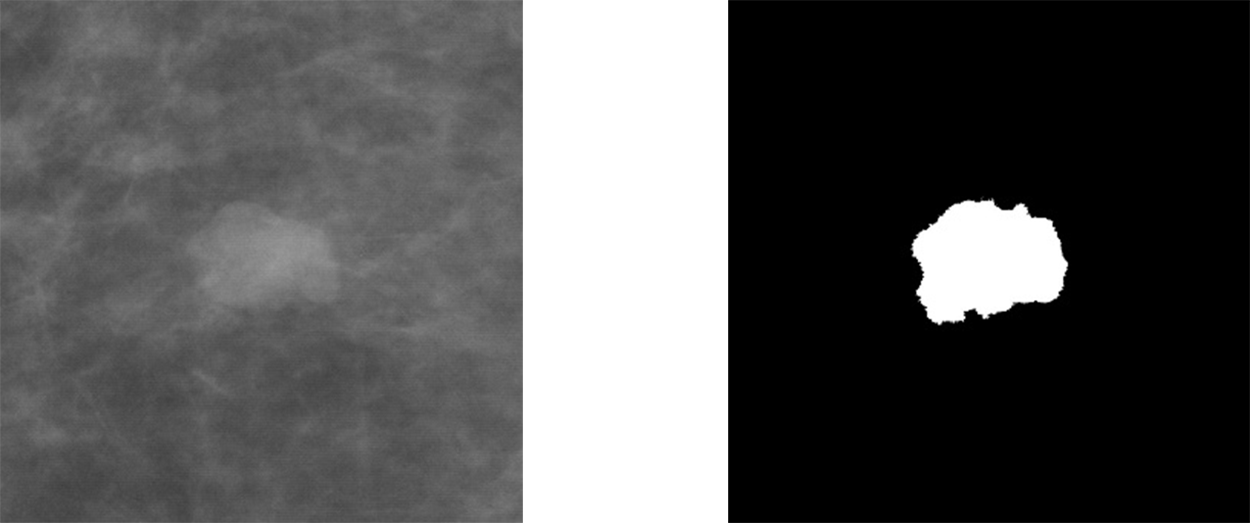

Pentru a înțelege structura rețelei U-Net este necesar să definim datele de intrare (eng. input) și datele de ieșire (eng. output). Așa cum am explicat mai sus, segmentarea presupune selectarea pixelilor care formează regiunea sau obiectul de interes. Acest lucru este reprezentat printr-o mască, o imagine binară, unde pixelii albi descriu obiectul căutat, iar pixelii negrii fundalul. Această imagine este de fapt outputul unei rețele de segmentare. Iar ca input, avem tot o imagine, care conține sau nu obiectul/regiunea de interes.

Figura 3 Exemplu de imagine și mască decupată